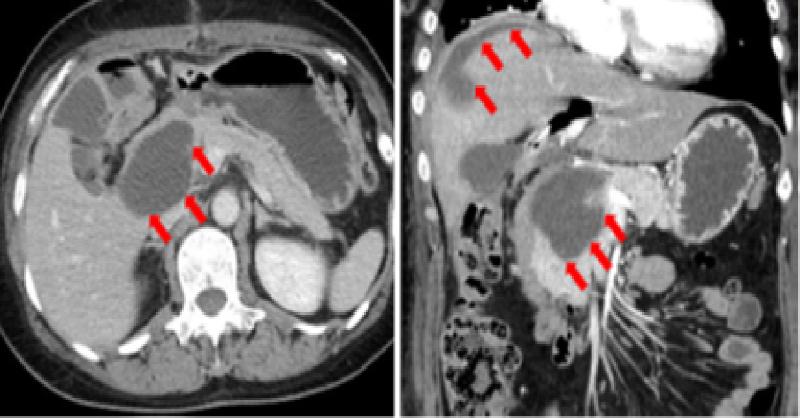

A 55-year-old woman underwent extrahepatic bile duct resection, including the gallbladder, and biliary tract reconstruction for Todani classification type IV-A CBD. The reconstruction method used was hepaticojejunostomy with Roux-en-Y. The drain was placed in the foramen of Winslow, dorsal of the anastomotic site. The patient started eating solid f